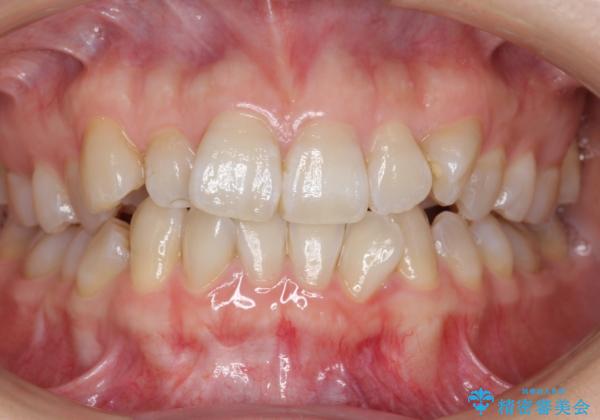

ハーフリンガル 犬歯のねじれ 歯根の外部吸収している歯を抜歯

- 前歯のねじれを主訴に来院。

上顎前歯も唇側傾斜しておらず、もともと叢生が多くない状態で上下左右を抜歯した上、リンガルで治療を行なったため、多少治療期間がかかりました。